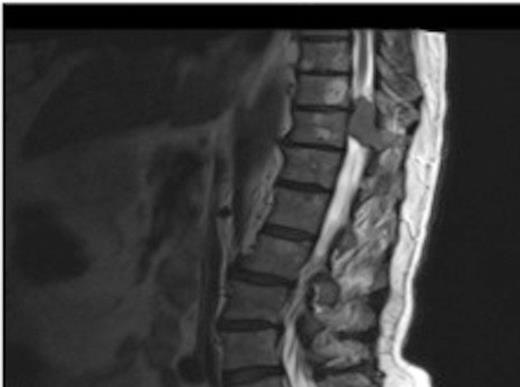

A one-year history of lower back pain, which was initially thought to be due to his liver metastasis, was investigated further with a full spine MRI scan. The scan revealed a large T10-11 extra-dural tumour with erosion of the T12 pedicle and extension into the soft tissue of the back. As a result of this discovery, the patient was referred for radiotherapy. Prior to commencement of this the oncologist requested a neurosurgical opinion from us.

MRI showing the T10-11 extra-dural tumour with erosion of the T12 pedicle